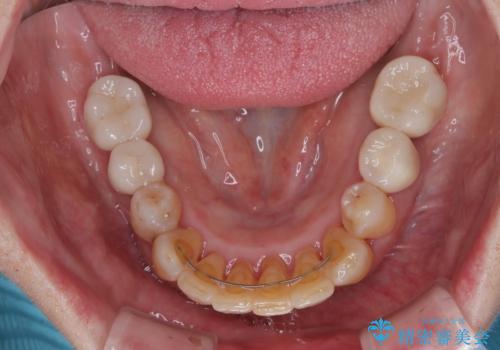

最終的に奥歯はオールセラミッククラウンによる補綴治療を行うこととしました。

治療前は磨き残しが多く見られ、全体的に歯肉が腫れている状態でしたが、抜歯の必要な歯を抜いたことで口腔内の環境が改善され、磨き残しも少なくなってきました。

インプラントにより咬合が回復したことで、治療開始時に認められた上顎前歯の動揺も改善されました。